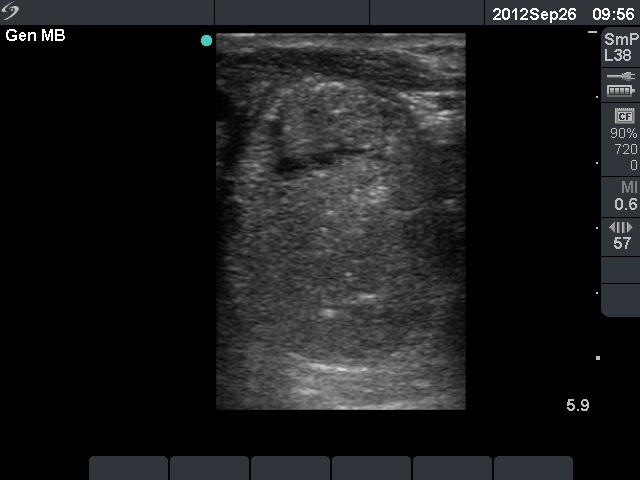

Ultrasonography. The right lobe was intact. The left lobe was extremely enlarged with the dimensions of 55x50x180 mm. It was composed of multiple hypoechogenic nodules which contained echonormal areas and cystic lesions. One of them is demonstrated on the ultrasonographic images.